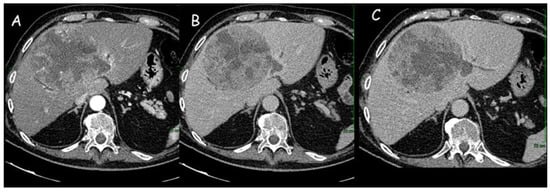

Classic CT features of iCCA include hypodense hepatic lesion without a capsule with dilatation of distal biliary ducts and, sometimes, capsular retraction due to the fibrotic nature of the tumor (Figure 1 and Figure 2).

Figure 1.

(A,B) Computed tomography imaging of intrahepatic cholangiocarcinoma (12 cm × 11 cm) of the right liver lobe: dishomogeneous enhancement in the arterial phase with hypodense areas of intralesional necrosis. (C) Dilatation of the peripheral intrahepatic biliary ducts.

Figure 2.

(A,B) Computed tomography imaging of an intrahepatic cholangiocarcinoma of approximately 8 cm in the left hepatic lobe, with capsular retraction, central hypodensity, and inhomogeneous enhancement due to necrotic-colliquative phenomena. Peripheral rim enhancement in the arterial phase (A) with progressive contrast filling in the subsequent phases (B). (C) Locoregional lymph nodes (white arrow).